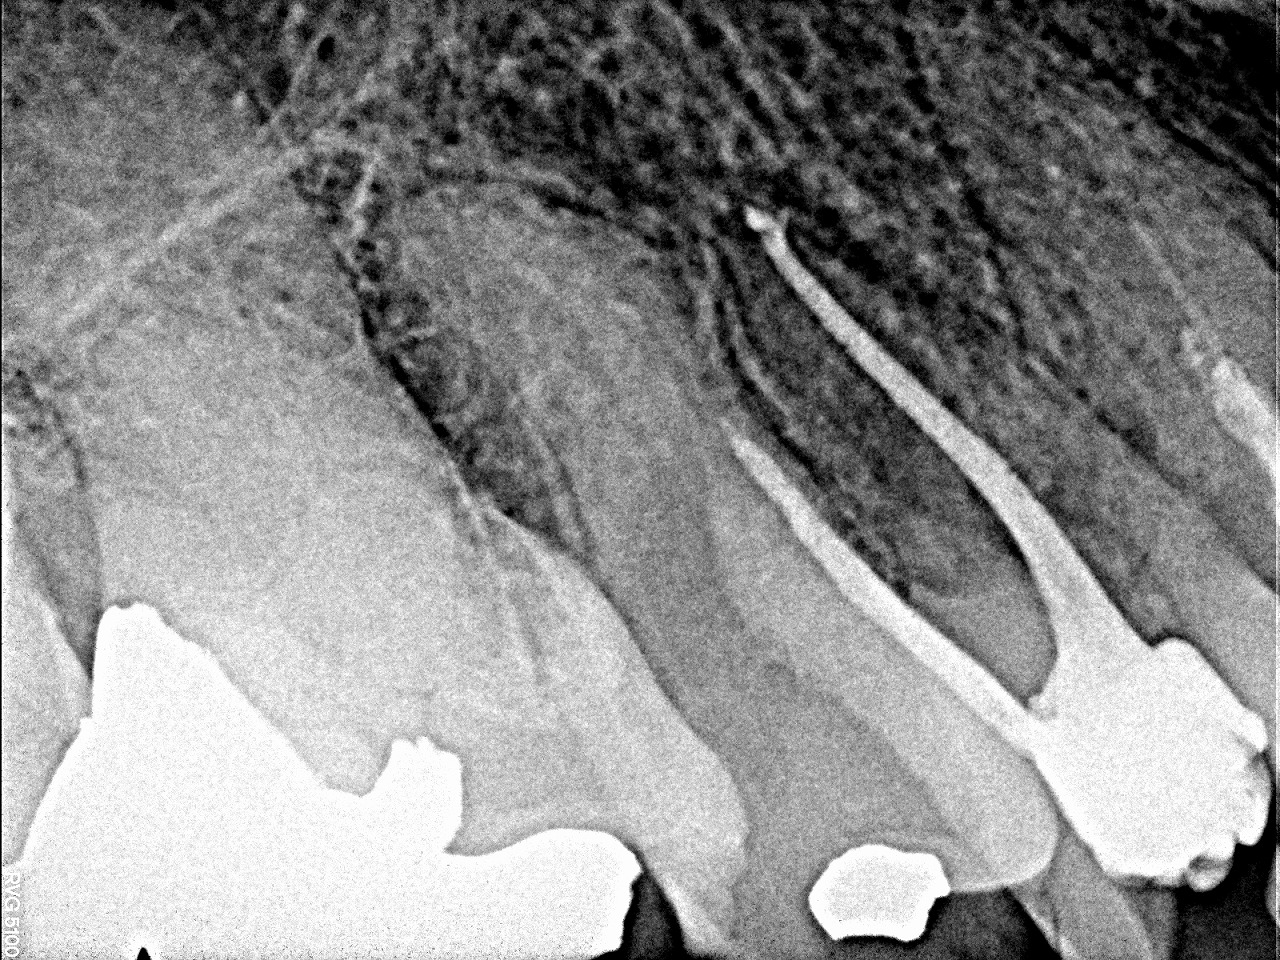

レントゲンになります

大きな虫歯もありません、

骨吸収が認められます

4番を根管内を開けてみると神経は失活していました

通法通り、先まで薬を詰めていきました